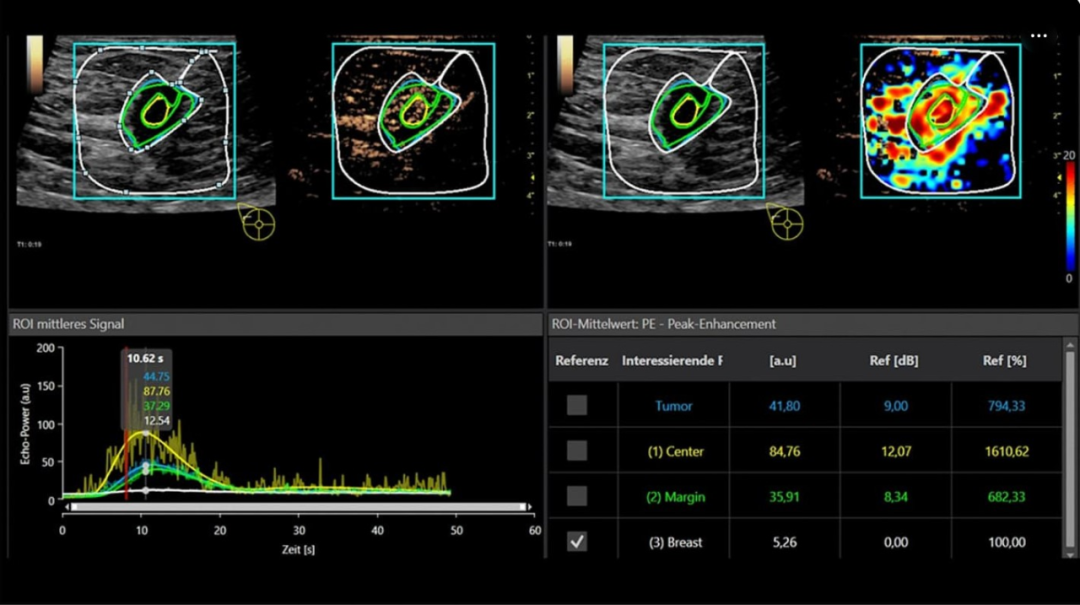

△ 乳腺病变的定量超声造影(CEUS)分析,显示峰值增强和曲线下区域的冲洗,以及相应的时间强度曲线和数值数据

CEUS在乳腺癌诊断中的独特价值体现在其能够评估肿瘤血管生成情况。

研究发现,恶性乳腺病变通常表现为"蟹爪样"增强、病变内超过两条增强血管以及周围丰富血管插入等特征。